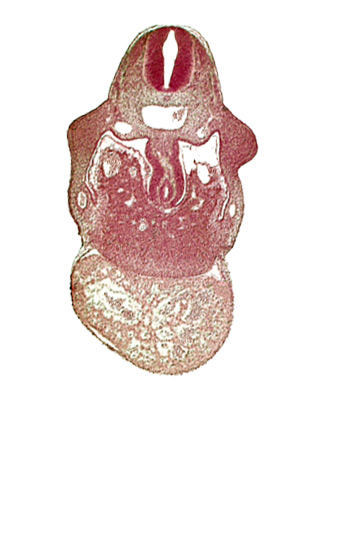

Carnegie Embryo #836 | Location: 08-02-03

Keywords: alar plate(s), basal plate, coelomic cavity, hepatic sinusoid, junction of duodenum and stomach primordia, left ventricle, pericardial cavity, postcardinal vein, right umbilical vein, right ventricle: endocardium, right ventricle: epimyocardium, septum transversum, specialized coelomic wall, upper limb bud

Source: The Virtual Human Embryo.